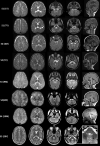

Hypomyelinating leukodystrophies comprise a subclass of genetic disorders with deficient myelination of the CNS white matter. Here we report four unrelated families with a hypomyelinating leukodystrophy phenotype harbouring variants in TMEM163 (NM_030923.5). The initial clinical presentation resembled Pelizaeus-Merzbacher disease with congenital nystagmus, hypotonia, delayed global development and neuroimaging findings suggestive of significant and diffuse hypomyelination. Genomic testing identified three distinct heterozygous missense variants in TMEM163 with two unrelated individuals sharing the same de novo variant. TMEM163 is highly expressed in the CNS particularly in newly myelinating oligodendrocytes and was recently revealed to function as a zinc efflux transporter. All the variants identified lie in highly conserved residues in the cytoplasmic domain of the protein, and functional in vitro analysis of the mutant protein demonstrated significant impairment in the ability to efflux zinc out of the cell. Expression of the mutant proteins in an oligodendroglial cell line resulted in substantially reduced mRNA expression of key myelin genes, reduced branching and increased cell death. Our findings indicate that variants in TMEM163 cause a hypomyelinating leukodystrophy and uncover a novel role for zinc homeostasis in oligodendrocyte development and myelin formation.